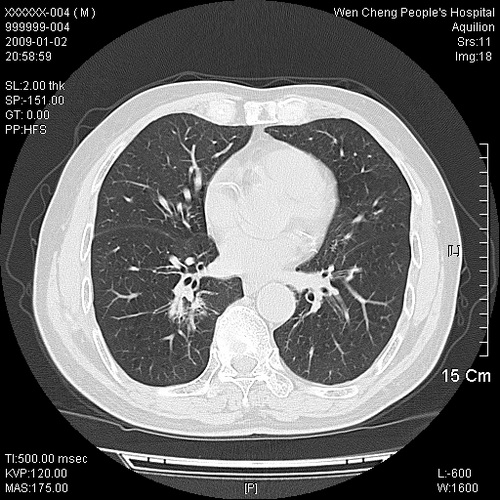

男性,73岁,有慢支病史,肿瘤系列标志物检验正常,血沉及血常规正常

右肺下叶背段小片状 磨玻璃样模糊影,内见血管及含气支气管像,支气管管壁增厚。考虑:慢性炎症!

右肺下叶背段小片状 实性与磨玻璃样影,内见血管及含气支气管像,支气管管壁增厚,边缘见长毛刺影。考虑:慢性炎症或肿瘤!建议抗炎治疗复查,密切观察随访!

右肺下叶片团状影内见扩张的含气支气管和支气管管壁增厚,其周有磨玻璃样模糊影和长毛刺。考虑慢性炎症可能性大。

2、右肺下叶片团状影内见扩张的含气支气管和支气管管壁增厚,其周有磨玻璃样模糊影和长毛刺。考虑周围型肺ca可能,结核不排。

高度提示细支气管肺泡癌,建议抗炎治疗半月观察病灶变化,如无明显改变,建议立即手术治疗.

病变形态非常不好呀,临床上血常规及症状也不明显,不太支持炎性病灶,高度警惕肿瘤病变,最好做个纤支镜检查。